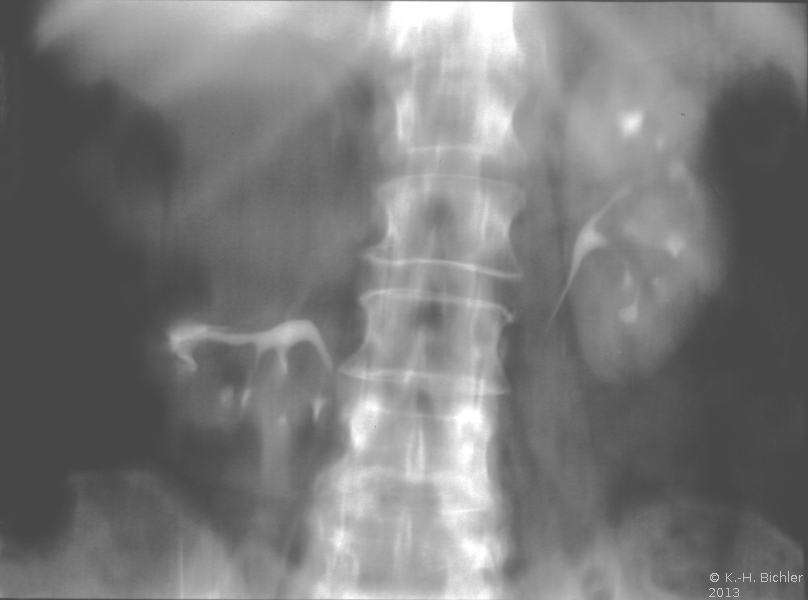

Die Patientin wurde beim Urologen wegen seit 3 Wochen persistierender Flankenschmerzen rechts vorstellig. Der Untersuchungsbefund zeigte als Auffälligkeit ein klopf- und druckschmerzhaftes Nierenlager rechts. Der Urinstatus wies keine Besonderheiten auf. Sonographisch fand der Urologe eine ca. 11 cm große einfache Nierenzyste rechts, die bis in das Nierenbecken reichte. Mit dem anschließend durchgeführten i.v.-Pyelogramm konnte eine Abflussbehinderung aus dem Nierenhohlraumsystem ausgeschlossen werden. Es waren jedoch glatt berandete, zystentypische Kelchausziehungen der oberen und mittleren Kelchgruppe zu erkennen. Der Urologe stellte die Patientin stationär in der Klinik vor. Zum Ausschluss eines eventuell vorliegenden zystischen Karzinoms wurde ein CT des Abdomens durchgeführt. Hier fand sich eine große, unkomplizierte Zyste, die die Niere verdrängte (Abbildung 4).